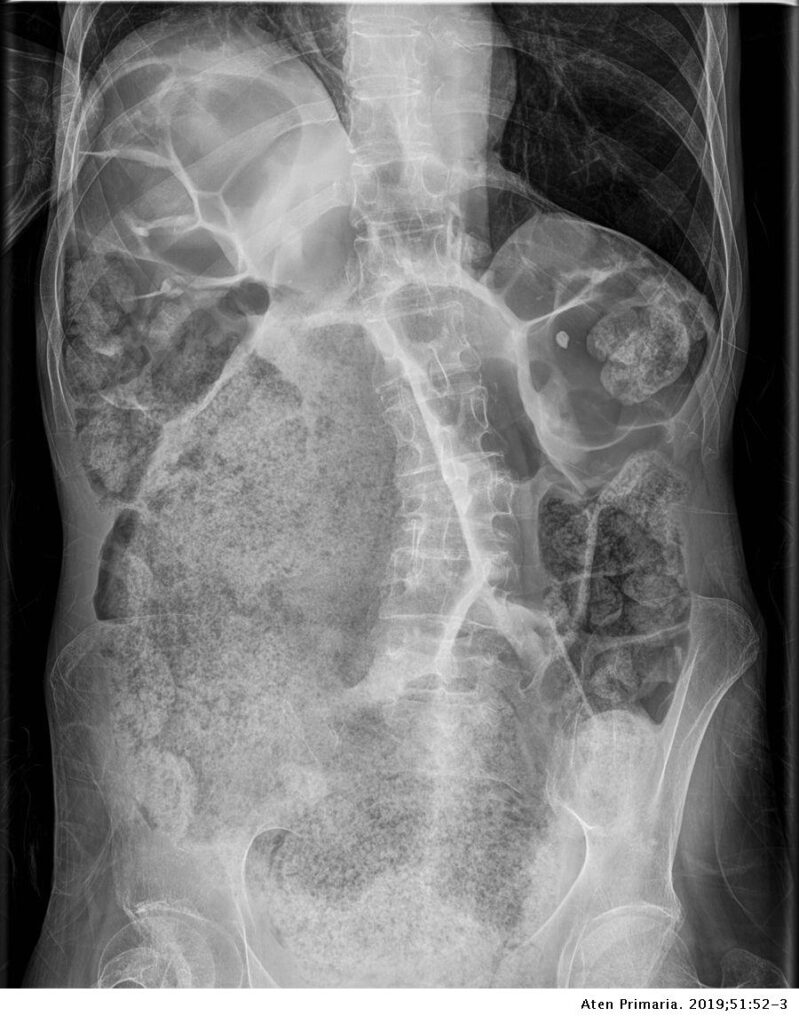

La retención fecal grave, que implica la acumulación excesiva y persistente de heces en la bóveda rectal, puede desencadenar una serie de consecuencias adversas en el sistema digestivo, incluyendo la posibilidad de obstrucción intestinal. Para entender en detalle cómo esta retención fecal puede llevar a una obstrucción adicional en el flujo fecal y a una oclusión parcial o total del colon, es necesario explorar los aspectos anatómicos y fisiológicos involucrados.

• Obstrucción mecánica: Cuando las heces se acumulan de manera significativa en la bóveda rectal, pueden formar una masa compacta y densa. Esta masa de heces puede crecer gradualmente y ocupar un espacio considerable en el recto y el colon. A medida que esta masa aumenta de tamaño, puede ejercer presión sobre las paredes intestinales y disminuir el espacio disponible para el paso de las heces no retenidas. Esta obstrucción mecánica puede dificultar o incluso impedir que las heces no retenidas avancen normalmente a través del colon.

• Distensión y dilatación: La acumulación prolongada de heces en el colon puede llevar a la distensión y dilatación de las secciones intestinales afectadas. Esta distensión puede agravar la obstrucción, ya que las secciones intestinales dilatadas pueden colapsar sobre sí mismas, estrechando aún más el lumen intestinal y dificultando el paso de las heces.

En conjunto, la retención fecal grave en la bóveda rectal puede ocasionar obstrucción adicional al flujo fecal debido a la compresión mecánica, la alteración de la peristalsis, la dificultad en la evacuación y la distensión del colon. Estos factores combinados pueden llevar a una obstrucción parcial o total del colon, lo que interfiere con la función normal del sistema digestivo y puede generar síntomas como dolor abdominal, distensión abdominal, náuseas y vómitos. La gestión temprana y adecuada de la retención fecal es esencial para prevenir estas complicaciones y garantizar el funcionamiento saludable del tracto gastrointestinal.